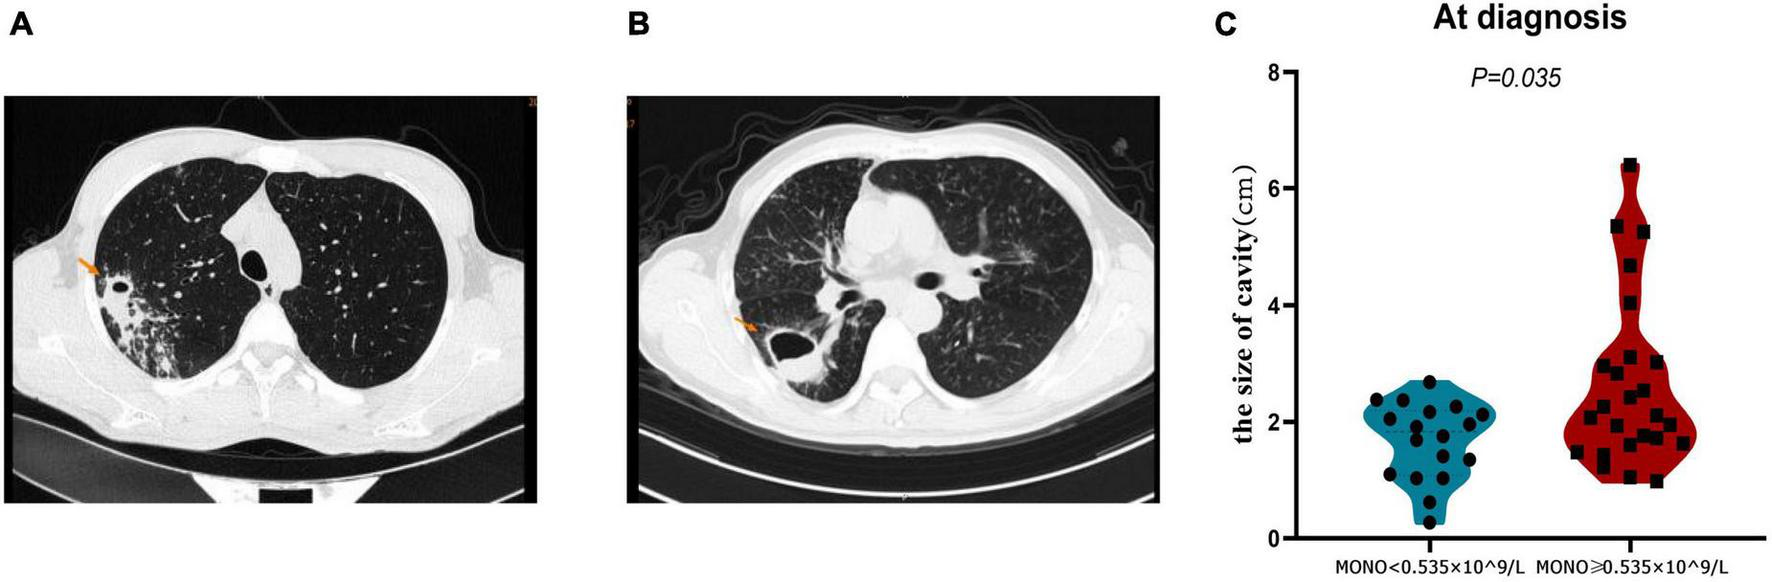

The closure of the pulmonary cavity in A-TB is an important indicator to judge the prognosis of patients (20). Therefore, we analyzed the cavity status of patients with monocyte < 0.535 × 10^9/L and monocyte ≥ 0.535 × 10^9/L in order to determine whether monocyte at baseline can also be used as a predictor of pulmonary cavity closure in A-TB. We analyzed the size of pulmonary cavities on admission in both groups, and patients with monocyte ≥ 0.535 × 10^9/L had relatively larger cavities compared with those with monocyte < 0.535 × 10^9/L (P = 0.035) (Figure 4).

FIGURE 4

Comparison of cavity size at diagnosis of TB in monocyte < 0.535 × 10^9/L and monocyte ≥ 0.535 × 10^9/L patients with TB and anemia. (A) Pulmonary imaging data of a patient in monocyte < 0.535 × 10^9/L group. (B) Pulmonary imaging data of a patient in monocyte ≥ 0.535 × 10^9/L group. (C) The cavity size in monocyte ≥ 0.535 × 10^9/L group was significantly larger than that in monocyte < 0.535 × 10^9/L group. MONO, monocyte.